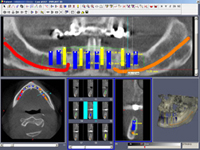

• Dokonalé vyšetření, stanovení diagnózy,naplánování ošetření - způsob, časový průběh,cena

Na implantologickém ošetření se podílí celý tým: lékař implantolog – zubní technik – dentální hygienistka – asistentka, kteří v případě potřeby spolupracují s dalšími odborníky: praktický zubní lékař (se svým týmem) – parodontolog – ortodont – obvodní lékař - internista – kardiolog – hematolog…

Zavedení implantátů do kosti je většinou ambulantní chirurgický výkon, srovnatelný s vytržením zubu a většinou se provádí v lokální anestézii. Ve výjimečných případech je možné použít i analgosedaci či celkovou narkózu. Operaci provádí zubní lékař-implantolog při dodržení všech podmínek sterility pro operaci. Nástroje pro tuto operaci jsou konstruovány tak, aby výkon byl šetrný vůči kosti a zavedení implantátu bylo provedeno ve velmi krátké době. Díky kvalitní anestézii je výkon nebolestivý. Aby byl pooperační otok co nejmenší, je potřeba operovanou oblast chladit, dle poučení ošetřujícího lékaře. Lékař také ordinuje podle potřeby léky na bolest, případně antibiotika.

Průměrná doba hojení implantátů před provedením definitivního protetického ošetření je 3-4 měsíce, v případech, kde je nutné doplnit chybějící kost (různé metody, postupy a materiály) – tzv. augmentace) se může doba hojení prodloužit na 8-12 měsíců. S tím je pacient vždy předem seznámen svým lékařem.